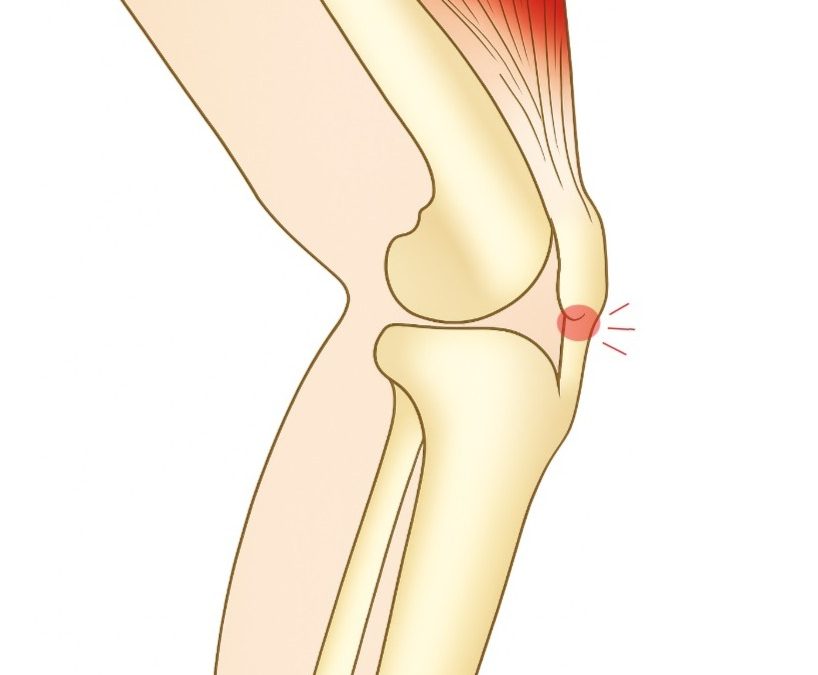

Under sommaren ökar både rörelseglädjen – och ibland belastningen på kroppen. Om du fått ont precis under knäskålen vid hopp, löpning eller trappgång kan det röra sig om hopparknä, en överbelastning i senan under knäskålen. Det är vanligt att symtomen förvärras när du...

Vi vet hur det känns: semestern närmar sig, skorna åker fram och löplusten spirar 🌞 Men om du går från stillasittande vardag till löpning flera gånger i veckan riskerar kroppen att säga ifrån. Vanliga sommarbesvär vi ser?🔸 Löparknä🔸 Hopparknä🔸 Hälsporre🔸...